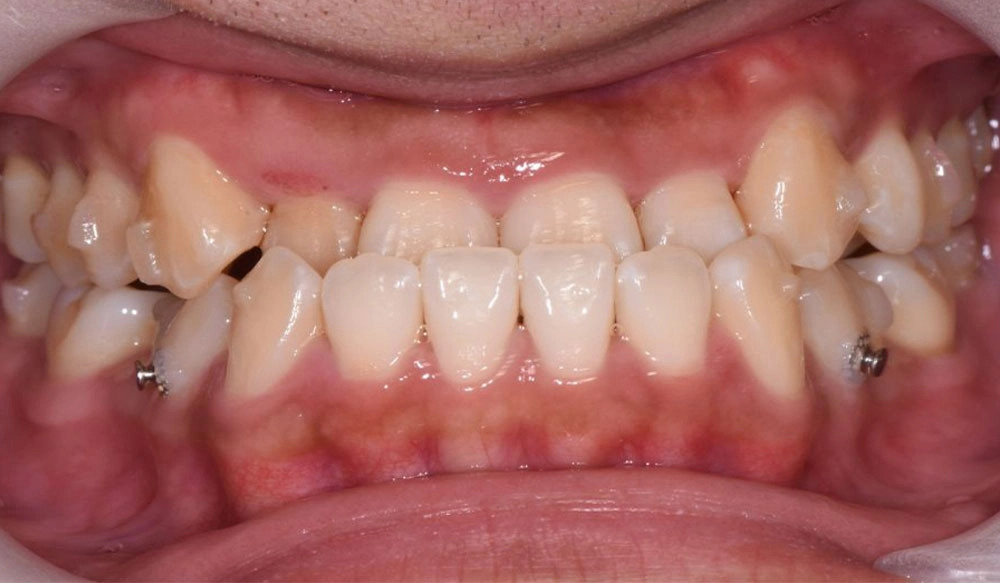

Crowding

Crowding is the condition in which there is a discrepancy between tooth size and space available for the teeth to be aligned in the dental arch

Patient Information:

Age: 17

Gender: female

Invisalign Treatment Option: Invisalign Comprehensive

Total Treatment Time:

29 months